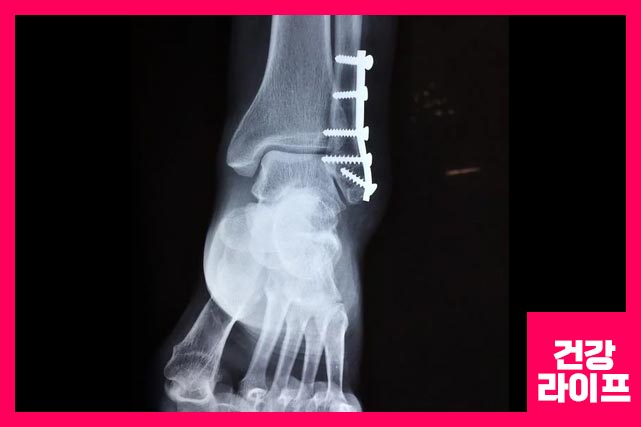

발목 골절

발목 골절은 경골이나 비골과 같은 발목에 있는 하나 이상의 뼈가 부러지는 것입니다. 발목 골절의 증상은 다음과 같습니다.

- 다리 전체에 퍼지는 통증

- 발목 부위 붓기

- 부상 부위에 물집

- 걷기 및 발 움직이기가 어려움

- 부러진 뼈가 피부를 밀고 있음